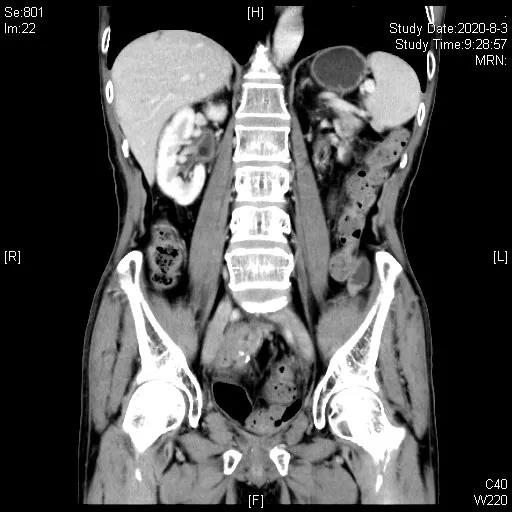

三线治疗:2020-05-25“培美曲塞700mg+阿帕替尼0.25gQD”治疗,期间腹腔造瘘口间断有极少量出血,鉴于患者停用抗生素已3月,于2020-06-19、07-11行“PD-1抑制剂(信迪利单抗)200mg+阿帕替尼0.25qd+培美曲塞0.7”治疗2周期,造瘘口出血停止,2020-08-03CT评估近期疗效:部分缓解(PR)。

三线治疗3周期后,影像学评估缩小,PR